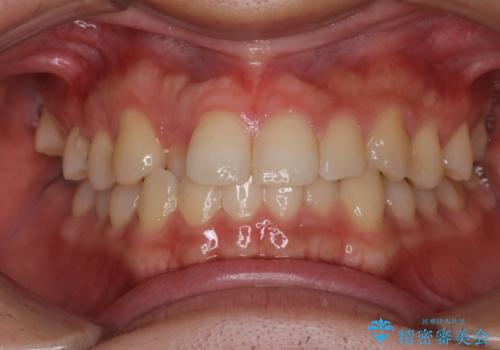

- 出っぱによる口元の閉じにくさを主訴に来院されました。上顎の出っ歯と上下顎叢生も認められたため、上下顎両側4番抜歯を行い、ワイヤー矯正で治療する治療計画を立てました。

上顎にはMI(マイクロインプラント)を埋入して固定源とすることで出っ歯の改善を図りました。

少しスペースクローズに時間がかかりましたが、MIを用いたワイヤー矯正で

主訴である出っ歯と叢生が改善されました。口も閉じやすくなり、スッキリとした口元になりました。